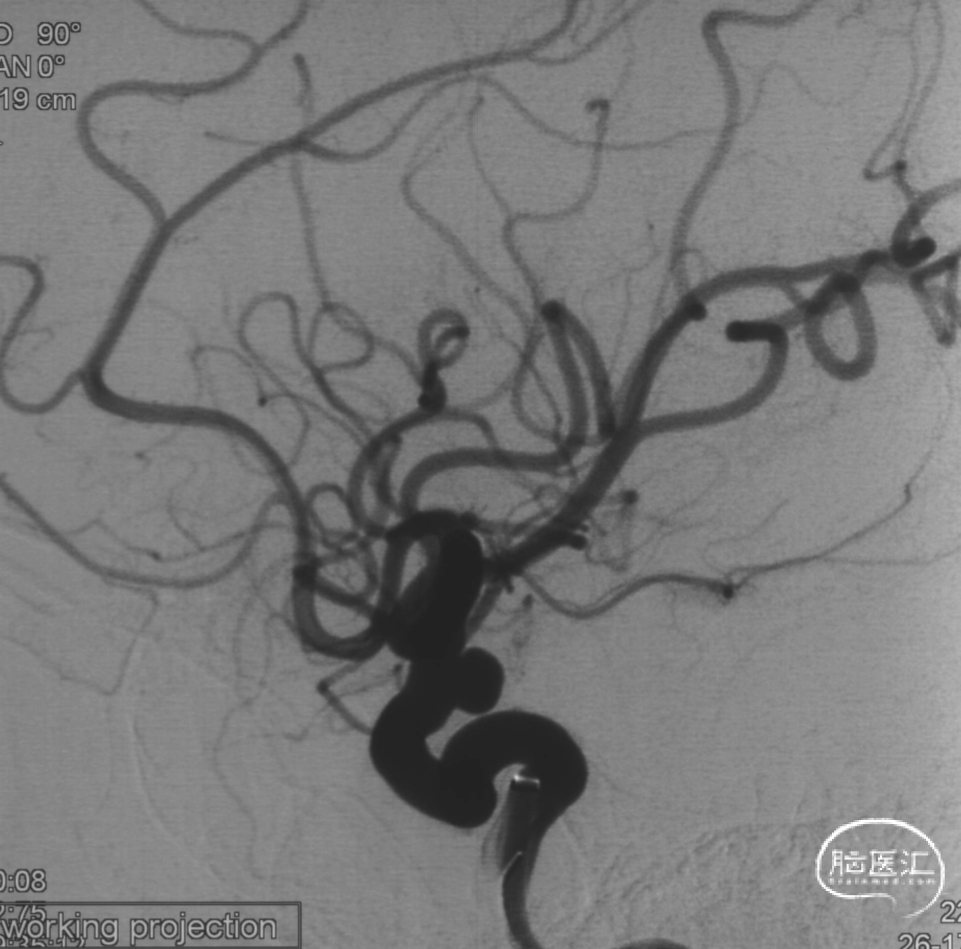

术后半年复查

5、FD植入后,动脉瘤明显造影剂瘀滞,效果显著。

6、Tubridge Plus材料改进后通体显影,可以更好观察支架的贴壁性及术中打开情况,提高释放安全性。

7、术后半年复查动脉瘤治愈,且未发生支架远近端狭窄及内膜过度增生,治疗效果满意。

8、同侧A1动脉瘤在FD保护下无变化。